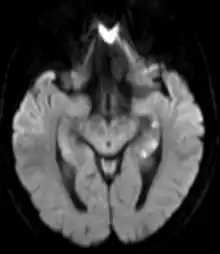

| Areas of hypoperfusion, seen above in the left sided hippocampus (seen as white punctate lesions on diffusion weighted MRI) are a characteristic finding in Transient Global Amnesia | |

There is no universally accepted diagnostic criteria for TGA, however proposed diagnostic criteria include: the absence of seizures, the absence of a head injury, symptoms that resolve within 24 hours, and the dysfunction or impairment being limited to amnesia (both retrograde and anterograde).[4] TGA is a clinical diagnosis and brain imaging or other testing is not required for the diagnosis.[4] However, brain imaging is often obtained to rule out other serious causes of sudden amnesia, including a stroke. Brain imaging is usually normal during and immediately after an episode of TGA. However delayed diffusion weighted MRI (obtained 12–48 hours after the episode) can sometimes show punctate lesions in the hippocampus (one of the areas of the brain responsible for memory) or adjacent areas of the brain. These lesions are transient; often persisting for several days after the episode.[4]

Functional MRI may show bitemporal hypoperfusion during an episode of TGA. Other areas affected include the hippocampus, parahippocampal gyrus, and amygdala.[4]